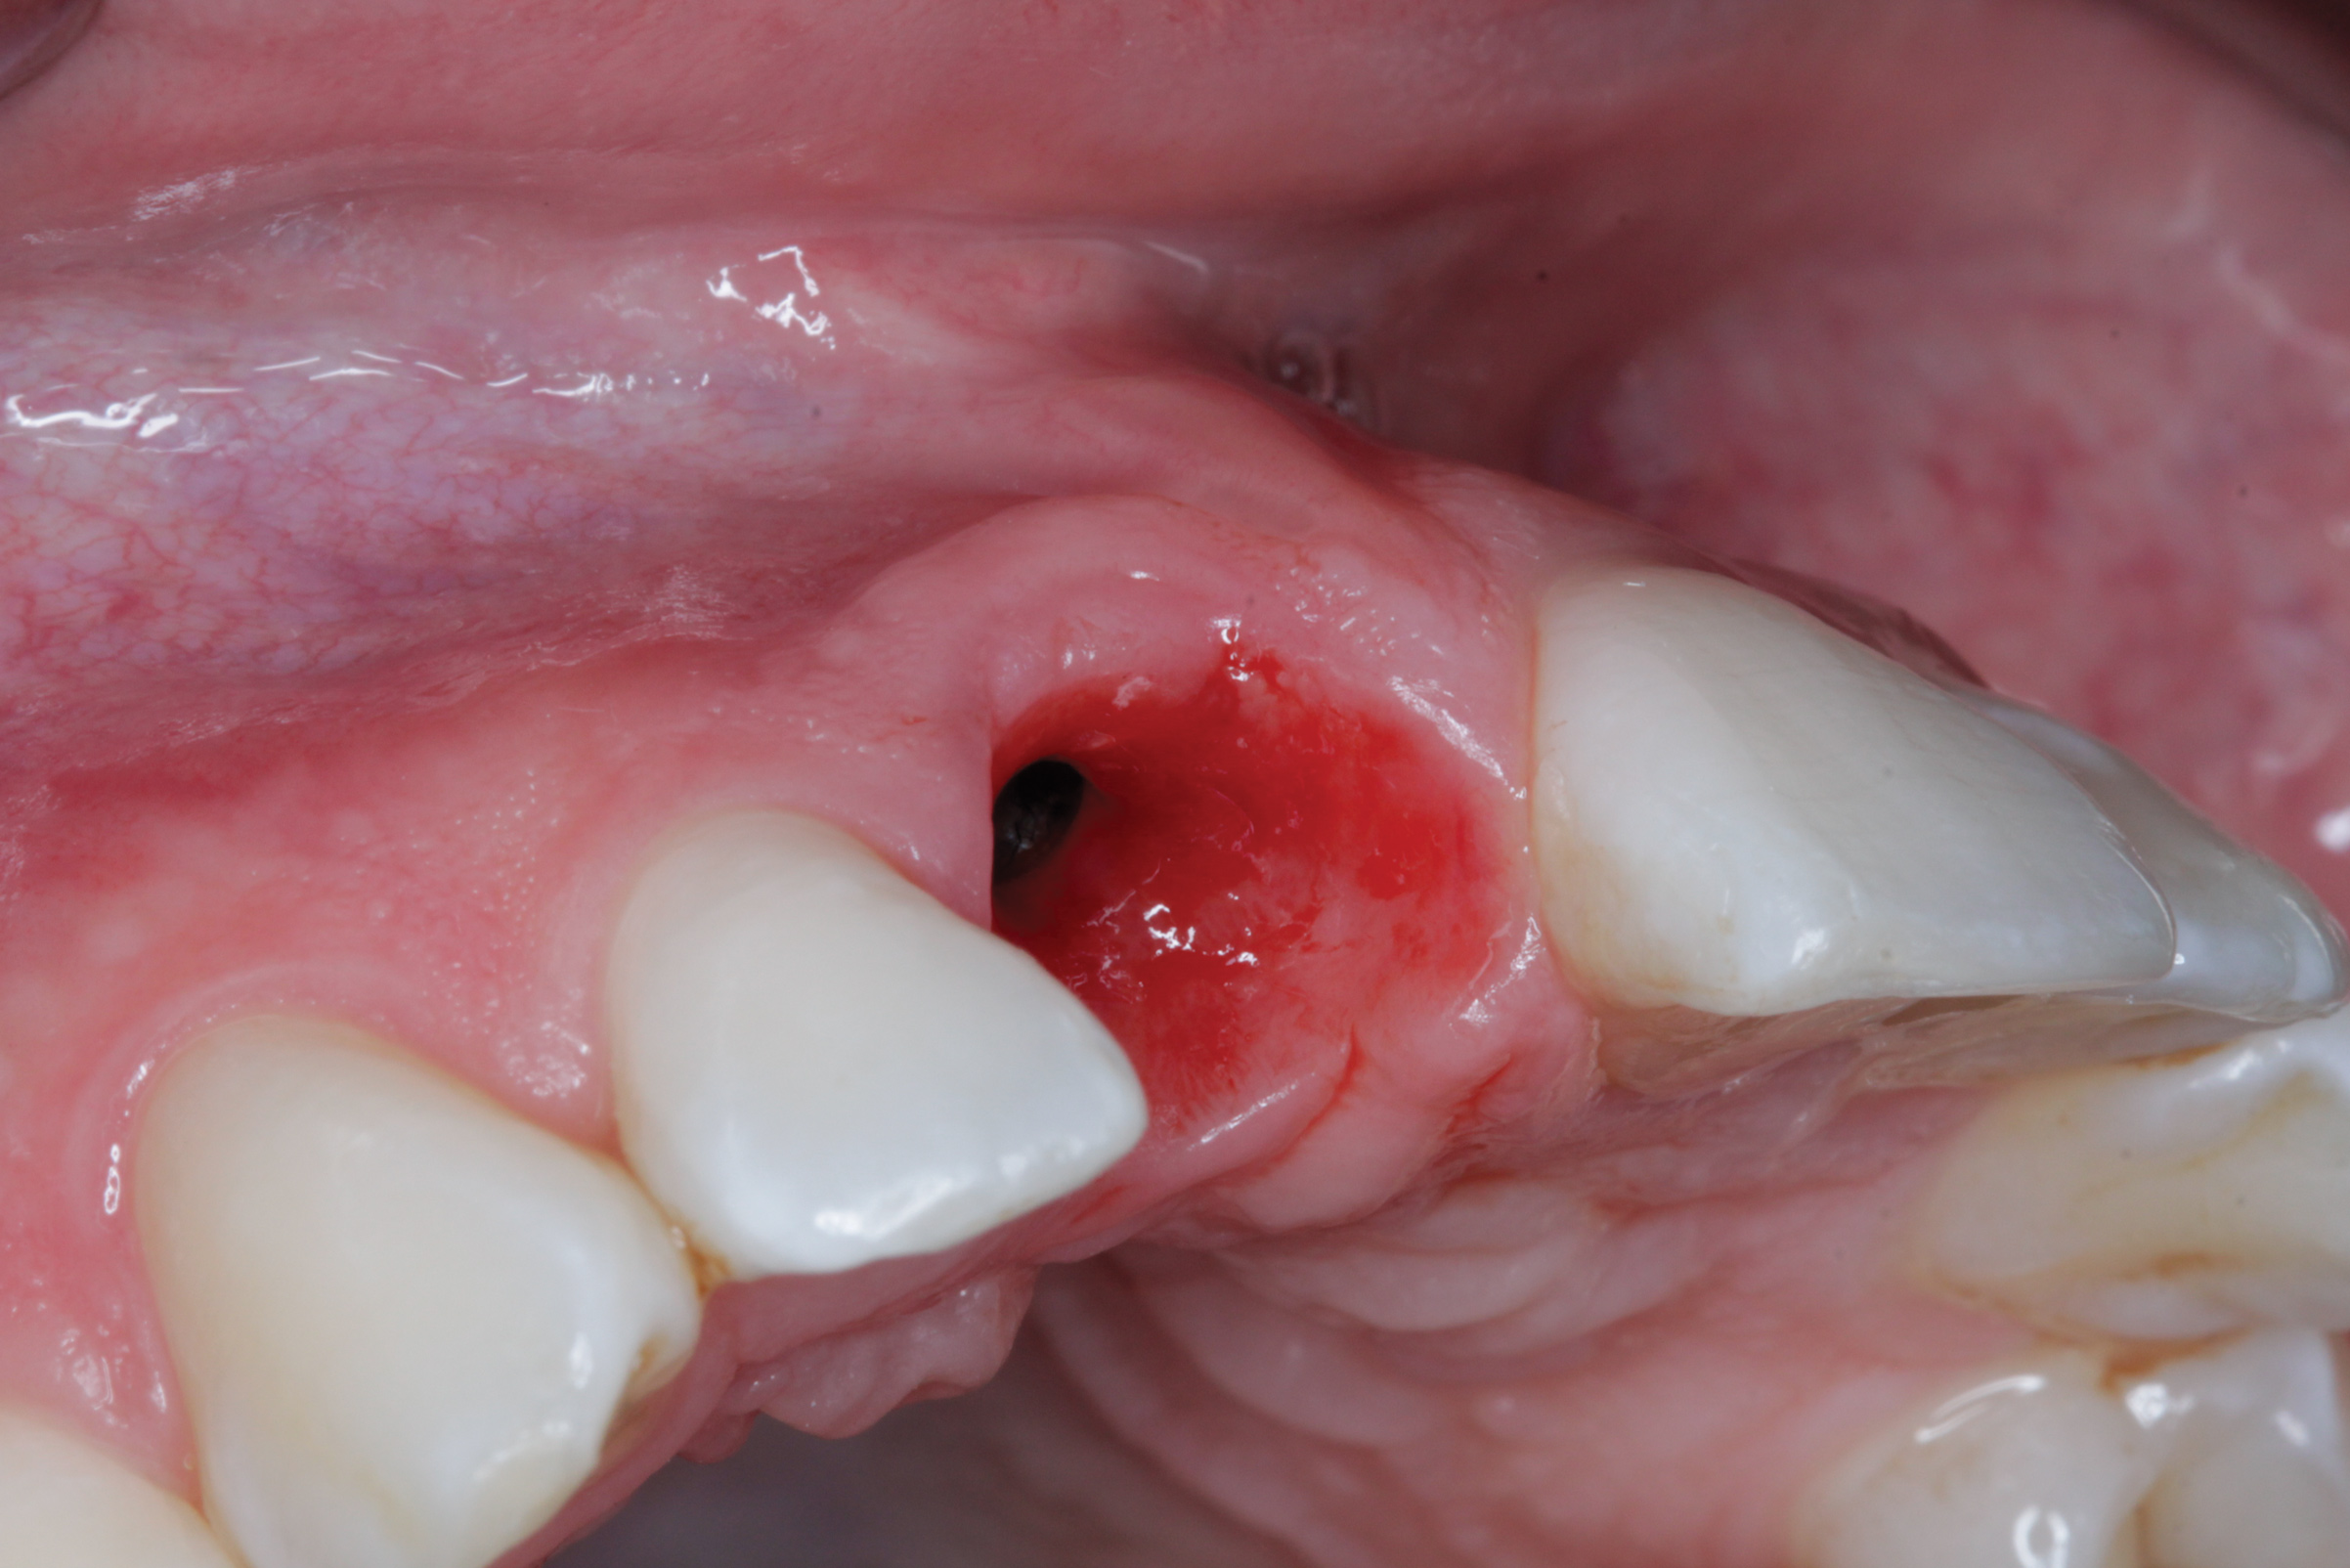

Fig 5. Emergence profile prior to insertion of definitive restoration.

Figure 5